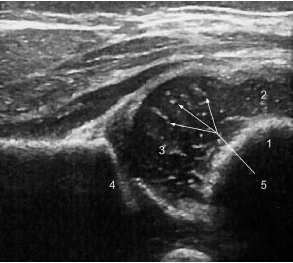

У новорожденных и детей до года проксимальный эпифиз бедренной кости, часть метафиза и большой вертел на эхограммах выглядят как одно слитное гипоэхогенное образование, так как состоят из неокостеневшего хряща. Эпифиз покрыт аваскулярным суставным гиалиновым хрящом, центральная зона состоит из эпифизарного гиалинового хряща, в котором присутствуют червеобразные эхосигналы, соответствующие кровеносным сосудам (рис. 1).

Рис. 1. Сонограмма тазобедренного сустава ребенка в возрасте 6 нед.: 1 — костно-хрящевая граница; 2 — большой вертел; 3 — головка бедренной кости; 4 — костная крыша вертлужной впадины; 5 — червеобразные эхосигналы, соответствующие сосудистым синусоидам / Fig. 1. Ultrasound image of the hip joint of a 6-week-old baby: 1 — chondro-osseous junction; 2 — greater trochanter; 3 — femoral head; 4 — bony acetabular roof; 5 — vermiform echo signals corresponding to vascular sinusoids